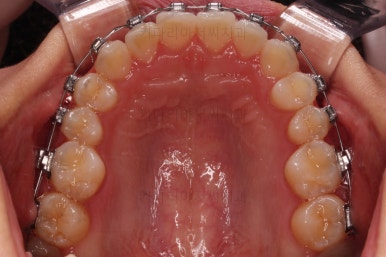

치료가 1년만에 종료가 되었네요.

치아가 가지런해졌고, 교합이 잘 맞는 모습이에요.

부산교정 전후사진을 비교해 볼게요.

치열의 모습이 좋아졌고, 웃을 때 보이는 치열이 가지런해서 미소도 훨씬 예뻐졌네요.

옆라인이라던지 입을 다물었을 때의 느낌은 원래도 좋으셨기 때문에 거의 그대로 유지가 되었고요.

1년정도 만의 만족스러운 치료였습니다.

이상 비발치로 덧니와 삐뚤한 앞니를 교정치료한 치료사례였습니다.